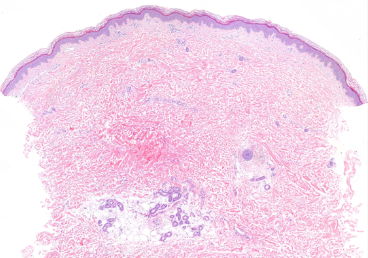

DERMATOHISTOPATHOLOGY:

Two 4 mm punch biopsies were performed on the left thigh. Hematoxylin and eosin staining revealed features consistent with no epidermal changes, edema in the upper dermis, minimal perivascular mononuclear infiltrate, and extravasated red blood cells in the upper dermis. Direct immunofluorescence (DIF) testing was negative.